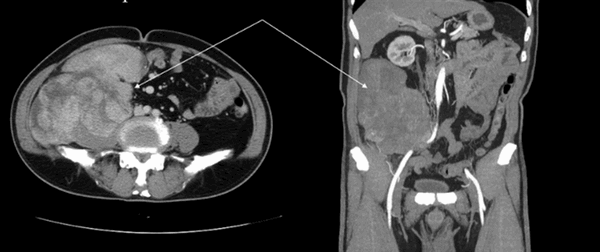

Гигантская опухоль забрюшинного пространства (стрелка) на КТ, сдавливающая правый мочеточник, наружные подвздошные артерии; умеренная гидронефротическая трансформация почки

Ультразвуковое и компьютерное сканирование позволяют поставить предварительный диагноз, магнитно-резонансную томографию назначают, если остались неразрешенные вопросы.

УЗИ малоинформативно в обнаружении опухолей менее 2-3 см и нечувствительно к мелким деталям, для надпочечников превышение указанных размеров с визуализацией зон некроза и очагов кальцификации рассматривают, как признак озлокачествления.

Перед планированием операции по поводу опухоли онколог назначает и КТ, и МР-сканирование ретроперитонеального пространства и брюшной полости как два взаимодополняющих способа обследования. Компьютерная томография лучше показывает метастазирование в кости скелета.